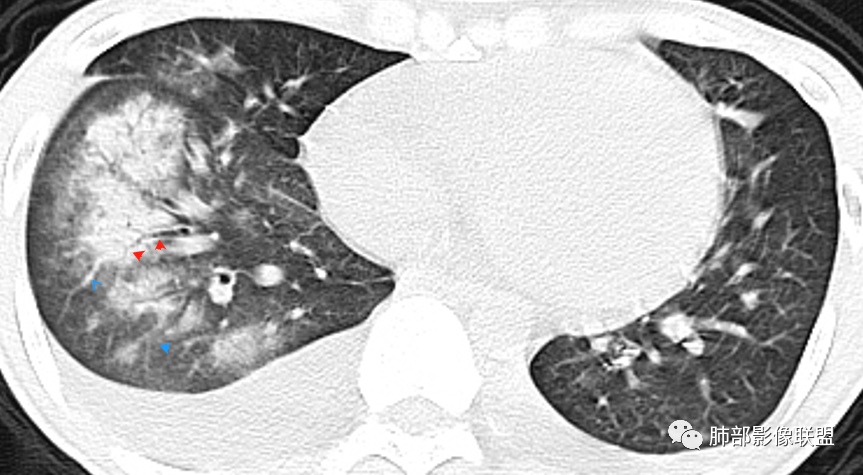

丽:青年男性,双下肢水肿,病史无肺部症状,化验白细胞明显减低;白蛋白低,提示双侧胸腔积液可能低蛋白所致。补体值降低提示自身免疫性疾病,影像见双肺散在结节样,斑片状高密度影及实变密度影,大部分沿支气管血管束分布,以右肺下叶为主,内可见充气支气管征,周围可见磨玻璃密度,并见多发小叶间隔增厚,伴心包少许积液,双肺病变,临床无症状,感染首先除外,结合腮腺病变,双下肢病变及化验检查,综合考虑自身免疫性疾病肺部改变

一切∮随缘:右肺多发大片状实变影,边界模糊,周围可见磨玻璃影,部分可见支气管穿行,支气管壁增厚,支气管扩张,血管束增粗,双肺多发结节,结节分布,以支气管束分布为主,双侧胸腔积液,心包积液,心包密度减低(贫血?),年轻男性,有下肢浮肿,实验室有血象及蛋白减低,考虑:1:病毒性肺炎2:GPA3:淋巴瘤

张延军:双肺多发斑片及结节状高密度影,边缘不清,结节周围伴晕征,前者沿支气管束分布呈实变影,内走形支气管通畅,临近肺组织见大片状磨玻璃影,界不清,中轴间质增厚,影像提示,支气管血管束周围及肺内间质为主病变,临床风免提示,考虑结蹄组织疾病肺内改变

南边:边界不清,内部支气管通畅

双侧胸腔积液,双下肺斑片状磨玻璃密度影,背景是大片状磨玻璃密度影,密度稍低一些。这个磨玻璃影非常弥漫,没有受局限,胸膜下不是很清楚,内部结构显示清楚,稍实变的区域也是,小叶间隔增厚,中轴间质也增厚。有些病变边缘有收缩,有轻度OP样特点,但是这些病变似乎密度非常均匀。

这类病变首先不是气道来源的,应该是沿间质分布,或者是肺泡腔内的病变。支气管壁周围增厚,磨玻璃影非常均匀,肺泡腔应该也有。